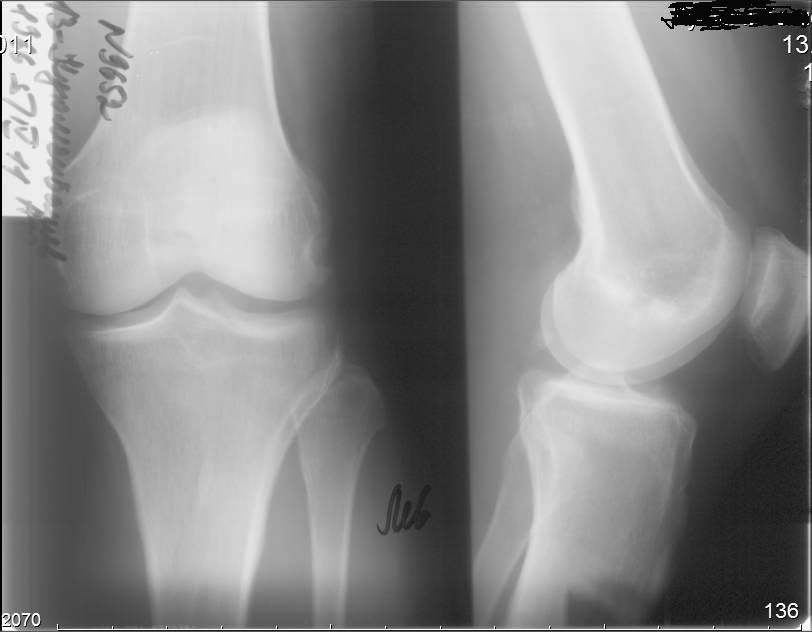

Пациент, мужчина, 45 лет. В 1982 году получил закрытый перелом диафиза бедренной кости справа. Результат консервативного лечения-варусная деформация бедренной кости В 1987 году выполнена вальгусная корригирующая остеотомия на уровне дистального эпифиза бедренной кости: варус бедренной кости нивелирован. Но в процессе лечения сформировалась выраженная контрактура в правом коленном суставе. Производилось 2 раза агрессивная разработка правого коленного сустава в аппарате типа Илизарова. В настоящее время беспокоят боли в области правого надколенника, при длительной ходьбе появляется ощущение скованности в 4-х главой мышце бедра, при отрыве правой стопы, голень и стопа как бы выбрасывается вперед (пациент, при этом, процесс разгибания в коленном суставе плохо контролирует). Правый коленный сустав внешне не деформирован, не отечен. Объем движений: сгибание до 90 градусов (до прямого угла, разгибание полное_180 гр. Сустав стабилен во всех плоскостях. Надколенник расположен практически на уровне суставной щели (тибиа-феморальной), малоподвижен, так называемая «игра надколенника» у пациента резко снижена . Пациент поступил в наше отделение для выполнения операции в объеме эндопротезирования правого коленного сустава. Однако, оценив коленный сустав, мы засомневались в необходимости данной операции этому пациенту. В данном случае , низкое стояние дегенеративно измененного правого надколенника нарушает функцию разгибательного аппарата правого коленного сустава и основная причина сосредоточена здесь, в надколеннике (по нашему мнению). У меня вопрос к коллегам: как деликатно, на нарушая разгибательный аппарат, помочь пациенту? Какие виды реконструктивных операции предпочтительны. С уважением Шушания Батал, ФБУ 3 ЦВКГ имени А А Вишневского

У вашего больного синдром Patella Baja или Patella Infera, т.е. низкое расположение надколенника. Состояние встречается в результате травмы или послеоперационных осложнении, например после коррегирующих операции. Сравнительные снимки показывает, что правый надколенник почти касается большеберцовую и укорочение связки приводит к нарушению пателло феморального взаймотношения. В результате такого нарушения начинается хондромаляция хрящевого покрова.

Оценка нарушении взаймосвязи высоты надколенника и собственной связки описана в методике Insall и Salvati, где в норме должен быть почти одинаковым по длине.